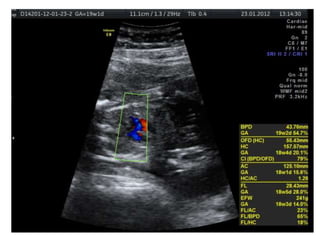

Down Syndrome: